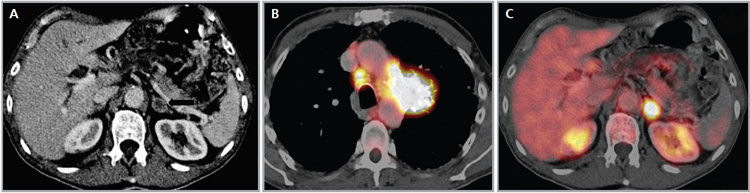

La gran mayoría de las lesiones malignas de la glándula suprarrenal presentan aumento en la captación del FDG (análogo de la glucosa) dado su mayor metabolismo glucídico; de modo contrario las masas benignas, no inflamatorias, no muestran captación significativa de este radiotrazador, como es el caso de los adenomas (Figura 15 a, b, c y d). Algunos estudios recientes reportan que el PET con FDG tiene una sensibilidad cercana al 100% y especificidad de aproximadamente un 80 a 100% en la diferenciación de lesiones benignas y malignas. La presencia de necrosis o hemorragia en una lesión maligna suprarrenal puede resultar en un falso negativo, así como también existe una baja sensibilidad en lesiones menores a 1 cm. En relación a los falsos positivos se ha reportado que un 5% de los adenomas y las lesiones de carácter inflamatorio-infeccioso pueden presentar leve captación del FDG.

El uso del PET incluido en un equipo de TC (PET-CT) ofrece claras ventajas con respecto al uso del PET en forma aislada, puesto que permite una mejor localización anatómica de las alteraciones metabólicas observadas, así como también puede incorporar la densitometría y las características de lavado ya descritas para la TC, lo que haría que tres de las técnicas más efectivas en la caracterización de las lesiones suprarrenales puedan combinarse en un solo estudio; bajo estas condiciones la sensibilidad y especificidad serían cercanas al 100%.

El PET-CT presenta utilidad en demostrar enfermedad oculta y enfermedad residual hipermetabólica cuando los hallazgos morfológicos son equívocos14. Esto cobra especial relevancia en casos en que la glándula suprarrenal es el único sitio de metástasis sospechado (Figura 21 a, b y c).